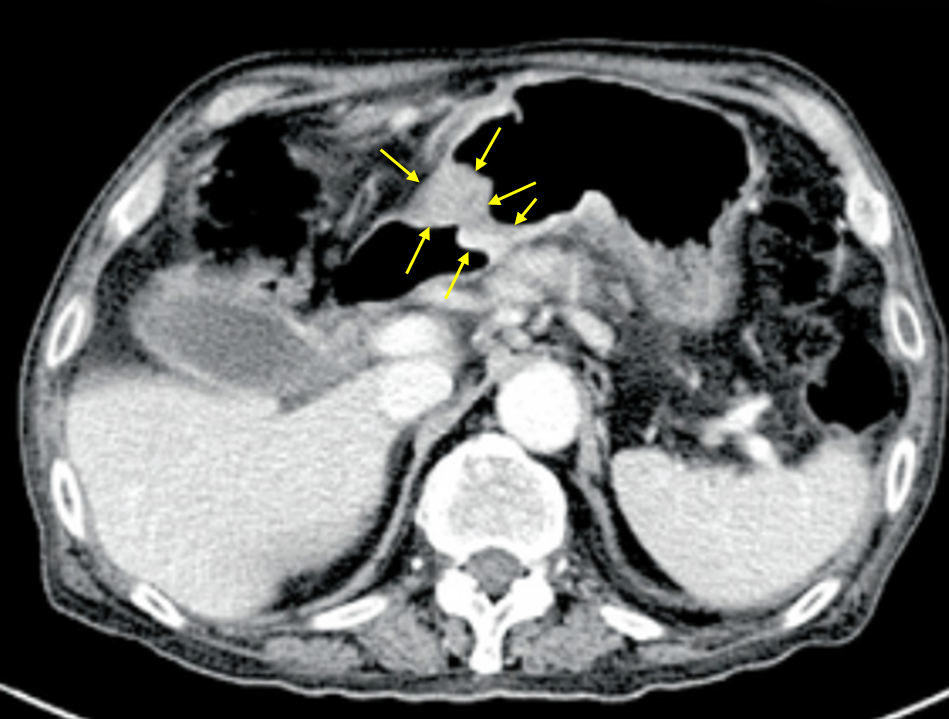

Img | EGD: 위의 distal part 위암, 음식물 Abdomen CT: Gastric outlet 부위 cancer |

임상양상 및 EGD 소견으로 보아 위암 의심 하, CT상 distant metastasis가 저명하지 않으므로 resectable하다고 판단, antrum~pylorus에 종양이 위치하므로 subtotal gastrectomy를 시행한다.

• 급격한 체중감소와 고령에서의 상부위장관 출혈은 malignancy시사하며, 임상양상 종합했을 때 EGD와 CT상 위의 distal part에 위암으로 보이는 mass가 관찰된다. 원격전이는 관찰되지 않으므로 수술 가능하며 distal part의 위암은 distal gastrectomy(≒ subtotal gastrectomy)을 시행한다.